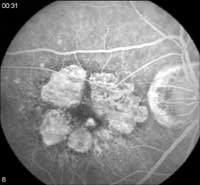

Occult CNV angiographic patterns don't conform to those seen with classic CNV (See Figure 3).

Fluorescein angiograms of occult CNV include fibrovascular pigment epithelium detachment (PED) and lesions that show leakage of undetermined source in late frames.

Fig. 3: Late-phase fluorescein angiograms of occult CNV show leakage of undetermined source. |